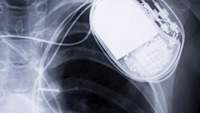

其他诱发因素包括人工心脏瓣膜、部分先天性心脏病、肥厚性心肌病、二尖瓣脱垂伴返流。当暴露于任何来源的感染时,具有这些危险因素的人更容易发生心内膜炎。

有细菌性心内膜炎诱发因素者(包括人工心脏瓣膜、既往细菌性心内膜炎、先天性心脏病、风湿性瓣膜功能障碍、肥厚性心肌病等)二尖瓣脱垂在大多数医疗或牙科手术之前,以及任何重大的皮肤感染发生时,应给予抗生素。你的医生会建议你在手术前服用何种抗生素,在某些情况下,在手术后服用何种抗生素。